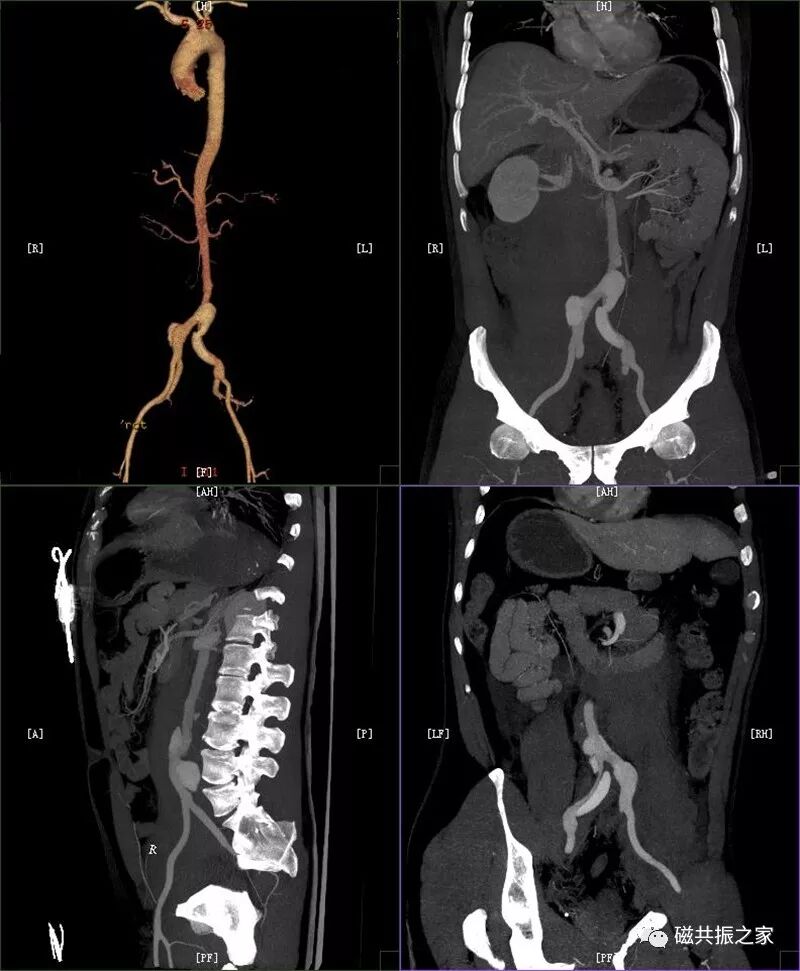

1.循环系统:主动脉夹层和胸腹主动脉瘤(破裂)、大量心包积液(血)。D:-CT-MR室资料新闻稿文件夹微信图片_20211127090743.jpg腰椎MRI扫描时发现的巨大腹主动脉瘤

图片D:-CT-MR室资料新闻稿文件夹微信图片_20211127090758.jpg血管壁内出血及夹层(CTA)